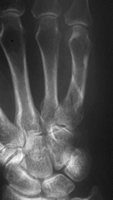

Stabilisierung der MHK Schaftfraktur. Übungsstabilität und freie Funktion der Hand sind postoperativ möglich.

Selbst eine basisnahe Fraktur läßt sich sofort und übungsstabil versorgen. Die Operation wird ambulant in iV-Lokalanästesie durchgeführt.